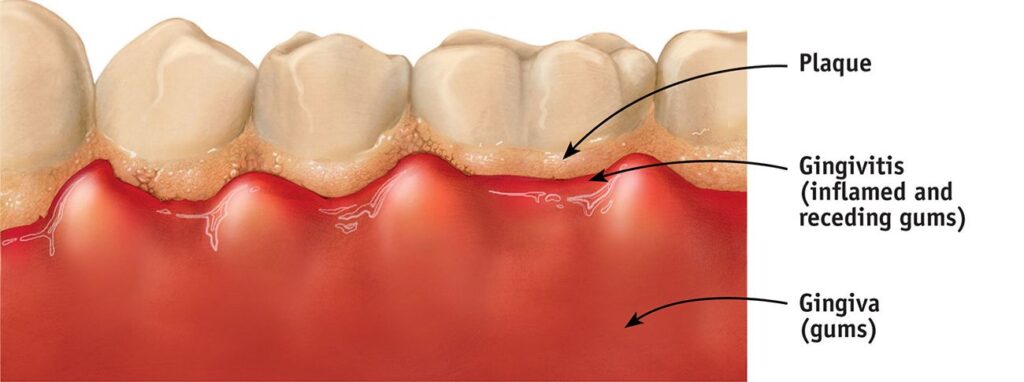

Yusuf,” he said, “there are some dirt and bacteria your toothbrush will never be able to remove.

When you leave them there, they harden into plaque, and over time, that plaque turns into tartar.

That’s why many people have bleeding gums or tooth decay even though they brush daily.”

Plaque hides between teeth and along your gumline where toothbrush bristles can’t reach

Missed Plaque Hardens Into Tartar

Plaque hardens into tartar that brushing or floss sticks can’t remove and once hardened, tartar can only be removed by a dentist.

You might think floss sticks are enough but they’re limited.

They can’t reach deep along the gumline or remove stubborn plaque.

That’s why more dentists now recommend water flossers.